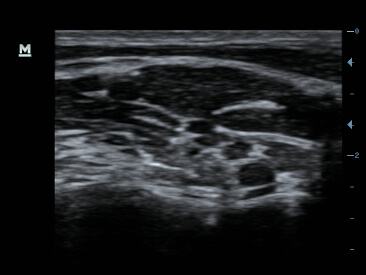

Im├Īgenes cl├Łnicas